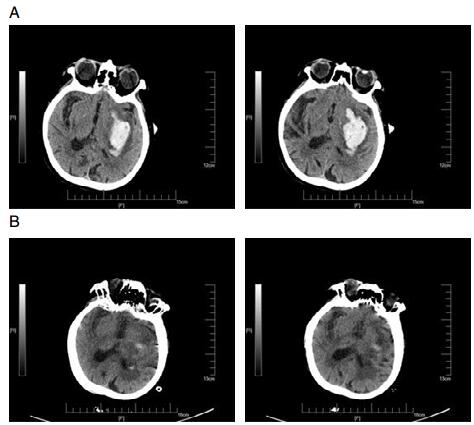

1.2 手术方法患者就诊后完善相关术前检查及准备工作。采用颅内血肿微创穿刺清除术,备皮后行CT定位,并避开颞浅动脉、颅内大血管(主要是外侧裂区及静脉窦)和重要功能区,根据CT图像,选取血肿最大层面,其上测量拟穿刺点头皮到血肿中心点的垂直距离选择相应长度的颅内血肿穿刺针(北京万特福公司生产的一次性使用颅内血肿清除套装)。床边监护、消毒、局麻后用尖刀片在拟穿刺点(血肿中心点在体表的投影点)切开头皮及皮下组织至颅骨,电钻钻穿颅骨后换上钝圆头针芯,手动将穿刺针插至血肿中心,拔除针芯,盖上螺帽,侧孔接引流管。第1次抽吸少于血肿的50%,抽吸完成后将穿刺针固定于颅骨部位,做好固定和标记;并注入尿激酶3~5万单位(溶解于5 mL生理盐水),注入后闭管2 h后开放,2次/d,必要时3次/d。手术过程中需注意抽吸时应使用等量生理盐水冲洗,以引流液清亮为标准,注意观察操作过程中患者生命特征变化并及时记录术中情况。根据每日引流量及术后CT判定拔针时间,拔管指征(一般2~3 d)有:术后复查CT提示颅内血肿清除大部(70%~80%)、引流液变少、颜色变浅变淡。

2 结果 2.1 三组患者血肿完全清除率及再出血发生率情况经过手术治疗后的三组患者,A组患者与B、C两组患者在血肿完全清除率上无明显差异,但是颅内再出血发生率明显低于B、C两组,差异具有统计学意义(P < 0.05,见表 1)。

3 讨论颅内出血是神经外科最常见的危急症之一,具有病死率高、致残率高、治愈率低的临床特点[10-12]。颅内血肿微创穿刺术在国内广泛开展,然而,不同穿刺时间点的选择对治疗效果的影响仍存在着争议[13-14]。本文为研究颅内血肿微创穿刺清除术治疗脑出血的最佳穿刺时间,回顾性对比分析了三组不同时间点手术患者的治疗效果,结果显示高血压脑出血患者超早期(4~6 h)行微创穿刺术,其术后再出血的发生率低于早期手术组及延期手术组,此研究结果和既往研究相反[15],可能与尿激酶超早期局部应用有关,也有可能超早期清除血肿,降低血肿对正常脑组织的不良反应及脑水肿的程度,具体分子机制有待进一步研究。同时超早期手术组患者平均住院时间明显短于早期手术组及延期手术组,术后随访结果显示超早期手术组的术后治疗效果明显优于早期手术组及延期手术组,超早期手术组中大多数患者能够在短期内恢复大部分的日常生活自理能力。